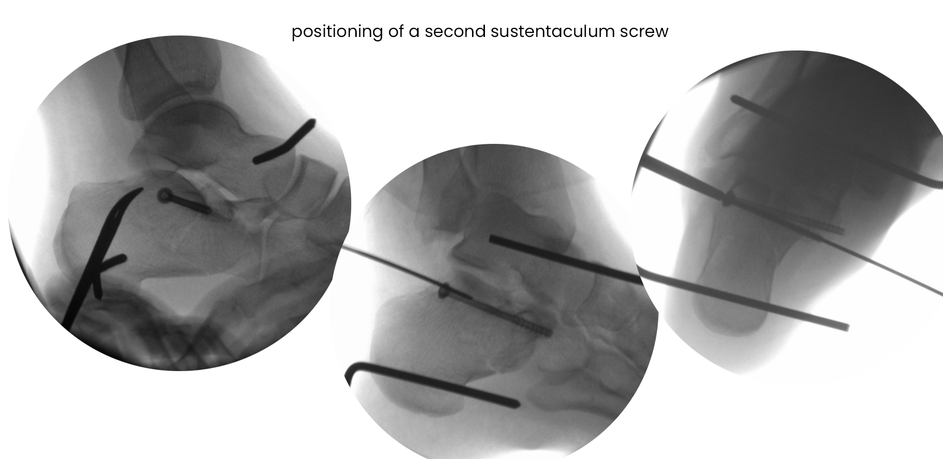

case 18ZJ, 23 years old, female, fall from horse, "atypical fracture" surgery after 2 days